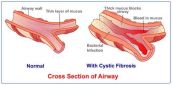

Bệnh u xơ nang là bệnh di truyền kéo dài suốt đời khiến cơ thể tiết mồ hôi và dịch nhầy. Nó có thể làm tắc nghẽn phổi và gây nhiễm trùng phổi. Để hiểu rõ hơn về bệnh lý này, mời các bạn tham khảo bài viết dưới đây!